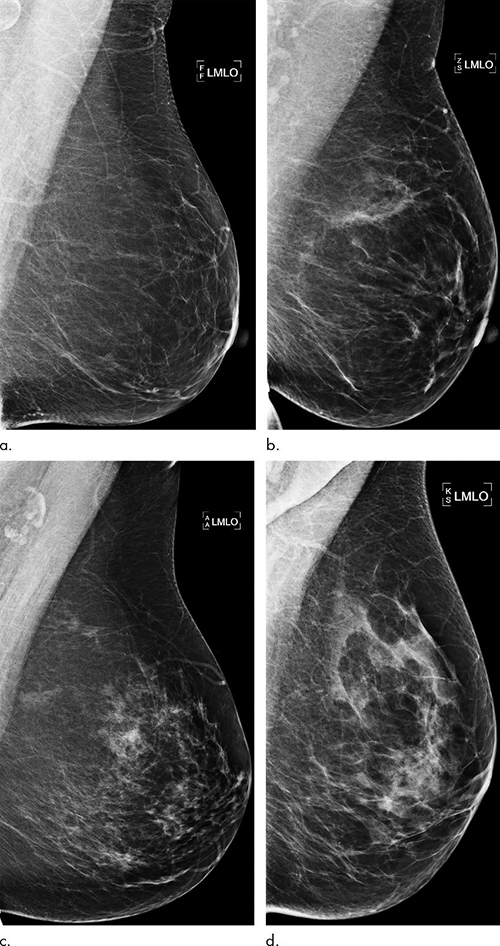

While high breast density may be incorporated into risk assessment, current prediction models may fail to fully take advantage of all the rich information found in mammograms. This information has the potential to identify women who would benefit from additional screening with MRI.

Dr. Dembrower and colleagues developed and trained a deep neural network risk model on mammograms from cases diagnosed between 2008 and 2012 and then studied on more than 2,000 women ages 40 to 74 who had undergone mammography in the Karolinska University Hospital system. Of the 2,283 women in the study, 278 were later diagnosed with breast cancer.

The deep neural network showed a higher risk association for breast cancer compared to the best mammographic density model (odds ratio: 1.6 and 1.3, respectively). The false-negative rate was lower for the deep neural network than for the best mammographic density model (31% vs. 36%; P = .006). The difference was most pronounced for women later diagnosed with more aggressive cancers.